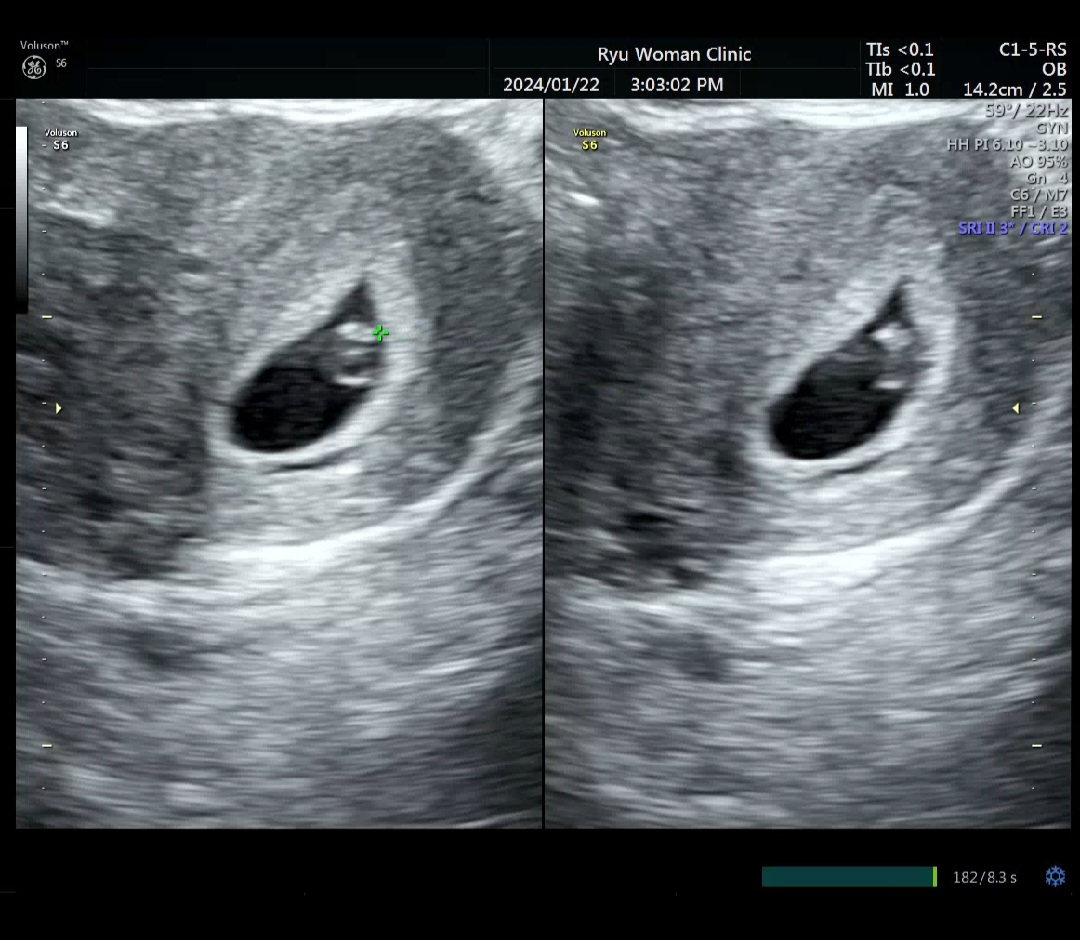

어제 심장소리 듣고왔어요~

1월 11일에 콩알만한 아기집보고 생리일 기준으론 5주지만 2주후에 아기 보이면 다시 예정일 잡아야겠다고~ 한 일주일정도 출산일 밀리겠다 하셨는데 어제 심소랑 아기랑 난황이랑 보고왔어요~ 애기 크기로 6주2일 된거 같다고 9월 8일 예정일이었는데 9월 14일로 정정해주셨어요 ㅎㅎ 입덧이 별로 없다 생각했는데 그냥 주기가 아니였던가봐요 울렁거리기 시작했어요....

와ㅎㅎ배아가 보이는 거 같아요^^ 저두 아기집만 보고 와서 2주 뒤를 기다리고 있는데 빨리 가서 더 큰 걸 보고싶어요ㅠㅠ 저도 그쯤되면 입덧을 하려나요ㅠ 지금은 전혀 없는데 말이죠^^;

축하드려요~~ 저도 어제 6주하고 3일 됐고 열매 심장소리 듣고 사진 받아왔어요~~ 출산 예정일 9월 13일인데!! 하루 차이나네요! 저도 아침마다 울렁거려서 아무것도 못먹겠어요ㅠ